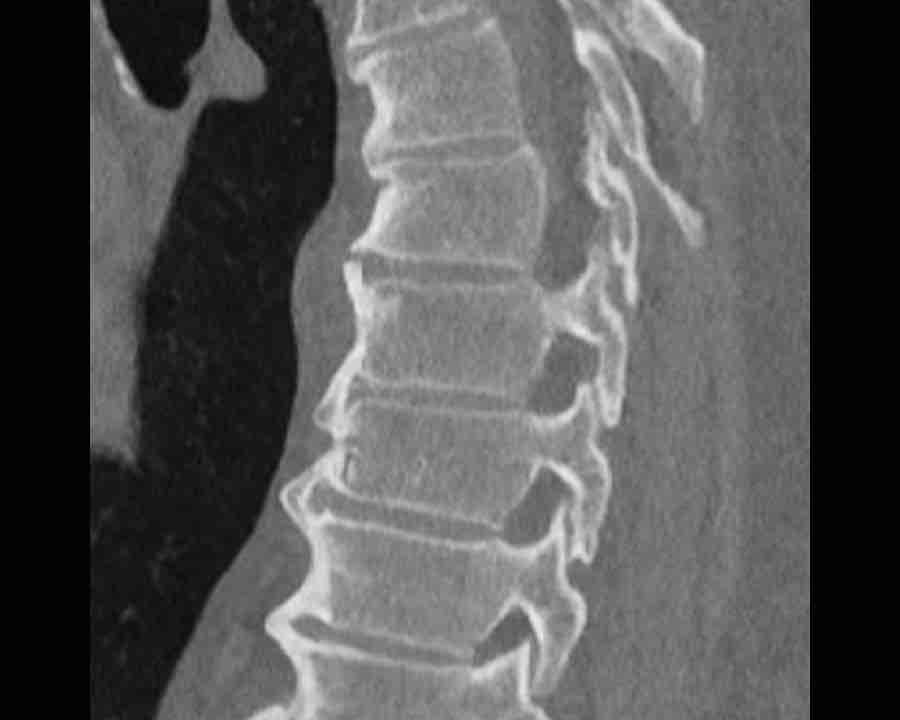

Scroll through images.

What are the findings?

Findings

- C injury? No.

- Signs of a rigid spine?

Yes (DISH), so a B3 injury is very likely. - A subtle fracture on the anterior vertebral body (arrows).

- No separation, probably due to positioning of patient in the scanner

Conclusion

Injury type B3.